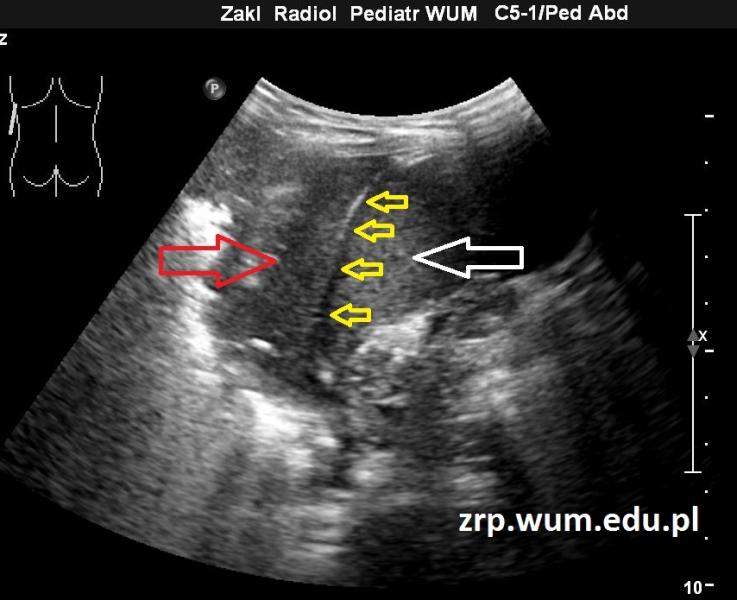

Przypadek 27: 5-letni pacjent zgłosił się do IP z powodu gorączki i bólu brzucha.

Rozpoznanie: W wykonanym badaniu USG jamy brzusznej stwierdzono masywne zmiany zapalne u podstawy płuca lewego, od tyłu; bez płynu w jamie opłucnowej. Czerwona strzałka - duży obszar bezpowietrznego miąższu płucnego u podstawy płuca lewego, żółte strzałki - przepona, biała strzałka - śledziona.